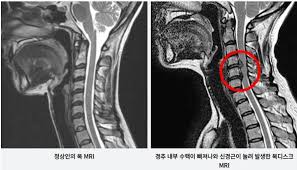

목디스크, 즉 경추디스크는 경추(목의 부분) 영역에서 발생하는 디스크 손상을 의미합니다. 이러한 디스크는 각 척추 사이에 위치하며, 척추의 충격을 흡수하고 유연성을 제공하는 중요한 역할을 합니다.

목디스크는 주로 디스크의 견봉이 손상되거나 내부의 젤이 누출됨으로써 발생합니다. 이런 손상은 디스크의 터짐, 미세한 틈새, 혹은 디스크에 가해지는 과도한 압력 때문에 발생할 수 있습니다

목디스크는 하중이 한 부위에 집중되어 경추 사이에 있는 추간판이 파열되고 내부의 수핵이 변위될 수 있는 상태를 가리킵니다.

이러한 상태는 공식적으로는 경추 추간판 탈출증으로 알려져 있으며, 목의 추간판이 손상되어 통증과 불편을 초래할 수 있습니다. 목디스크는 일상 활동에서의 부적절한 자세나 무리한 운동, 또는 직업적 요인으로 발생할 수 있습니다.